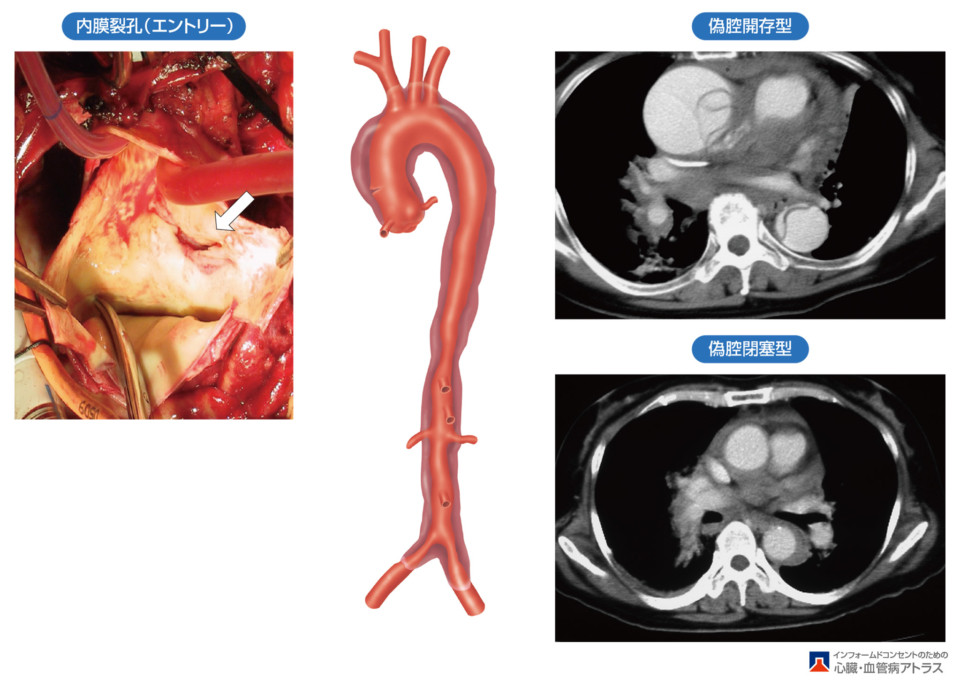

大動脈の壁は3層構造(内側から、内膜・中膜・外膜)をしています。動脈硬化などの要因で内膜・中膜に亀裂を生じ、外膜と中膜の間に血液が流入した状態をいいます(図3)。

大動脈解離を生じた範囲によって以下の2つのタイプに分類されます。

A型:上行大動脈(心臓をでてすぐの部分の大動脈)に解離がある場合

冠動脈(心臓自体を栄養する血管)や脳への血流を維持するための血管および心臓の弁などが上行大動脈の周辺にあり、致命的な合併症を生じる可能性が高いため、緊急手術の適応になります。

B型:上行大動脈に解離がなく、それより先から解離がある場合

腸や腎臓、下肢などへの血流障害、破裂がなければ安静、血圧管理を行います。

図3 . 急性A型大動脈解離の例